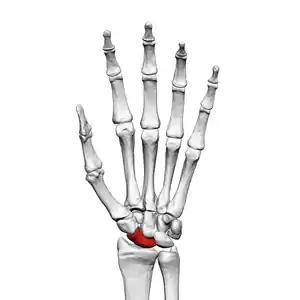

Scaphoid bone

Left hand anterior view (palmar view). Scaphoid bone shown in red.